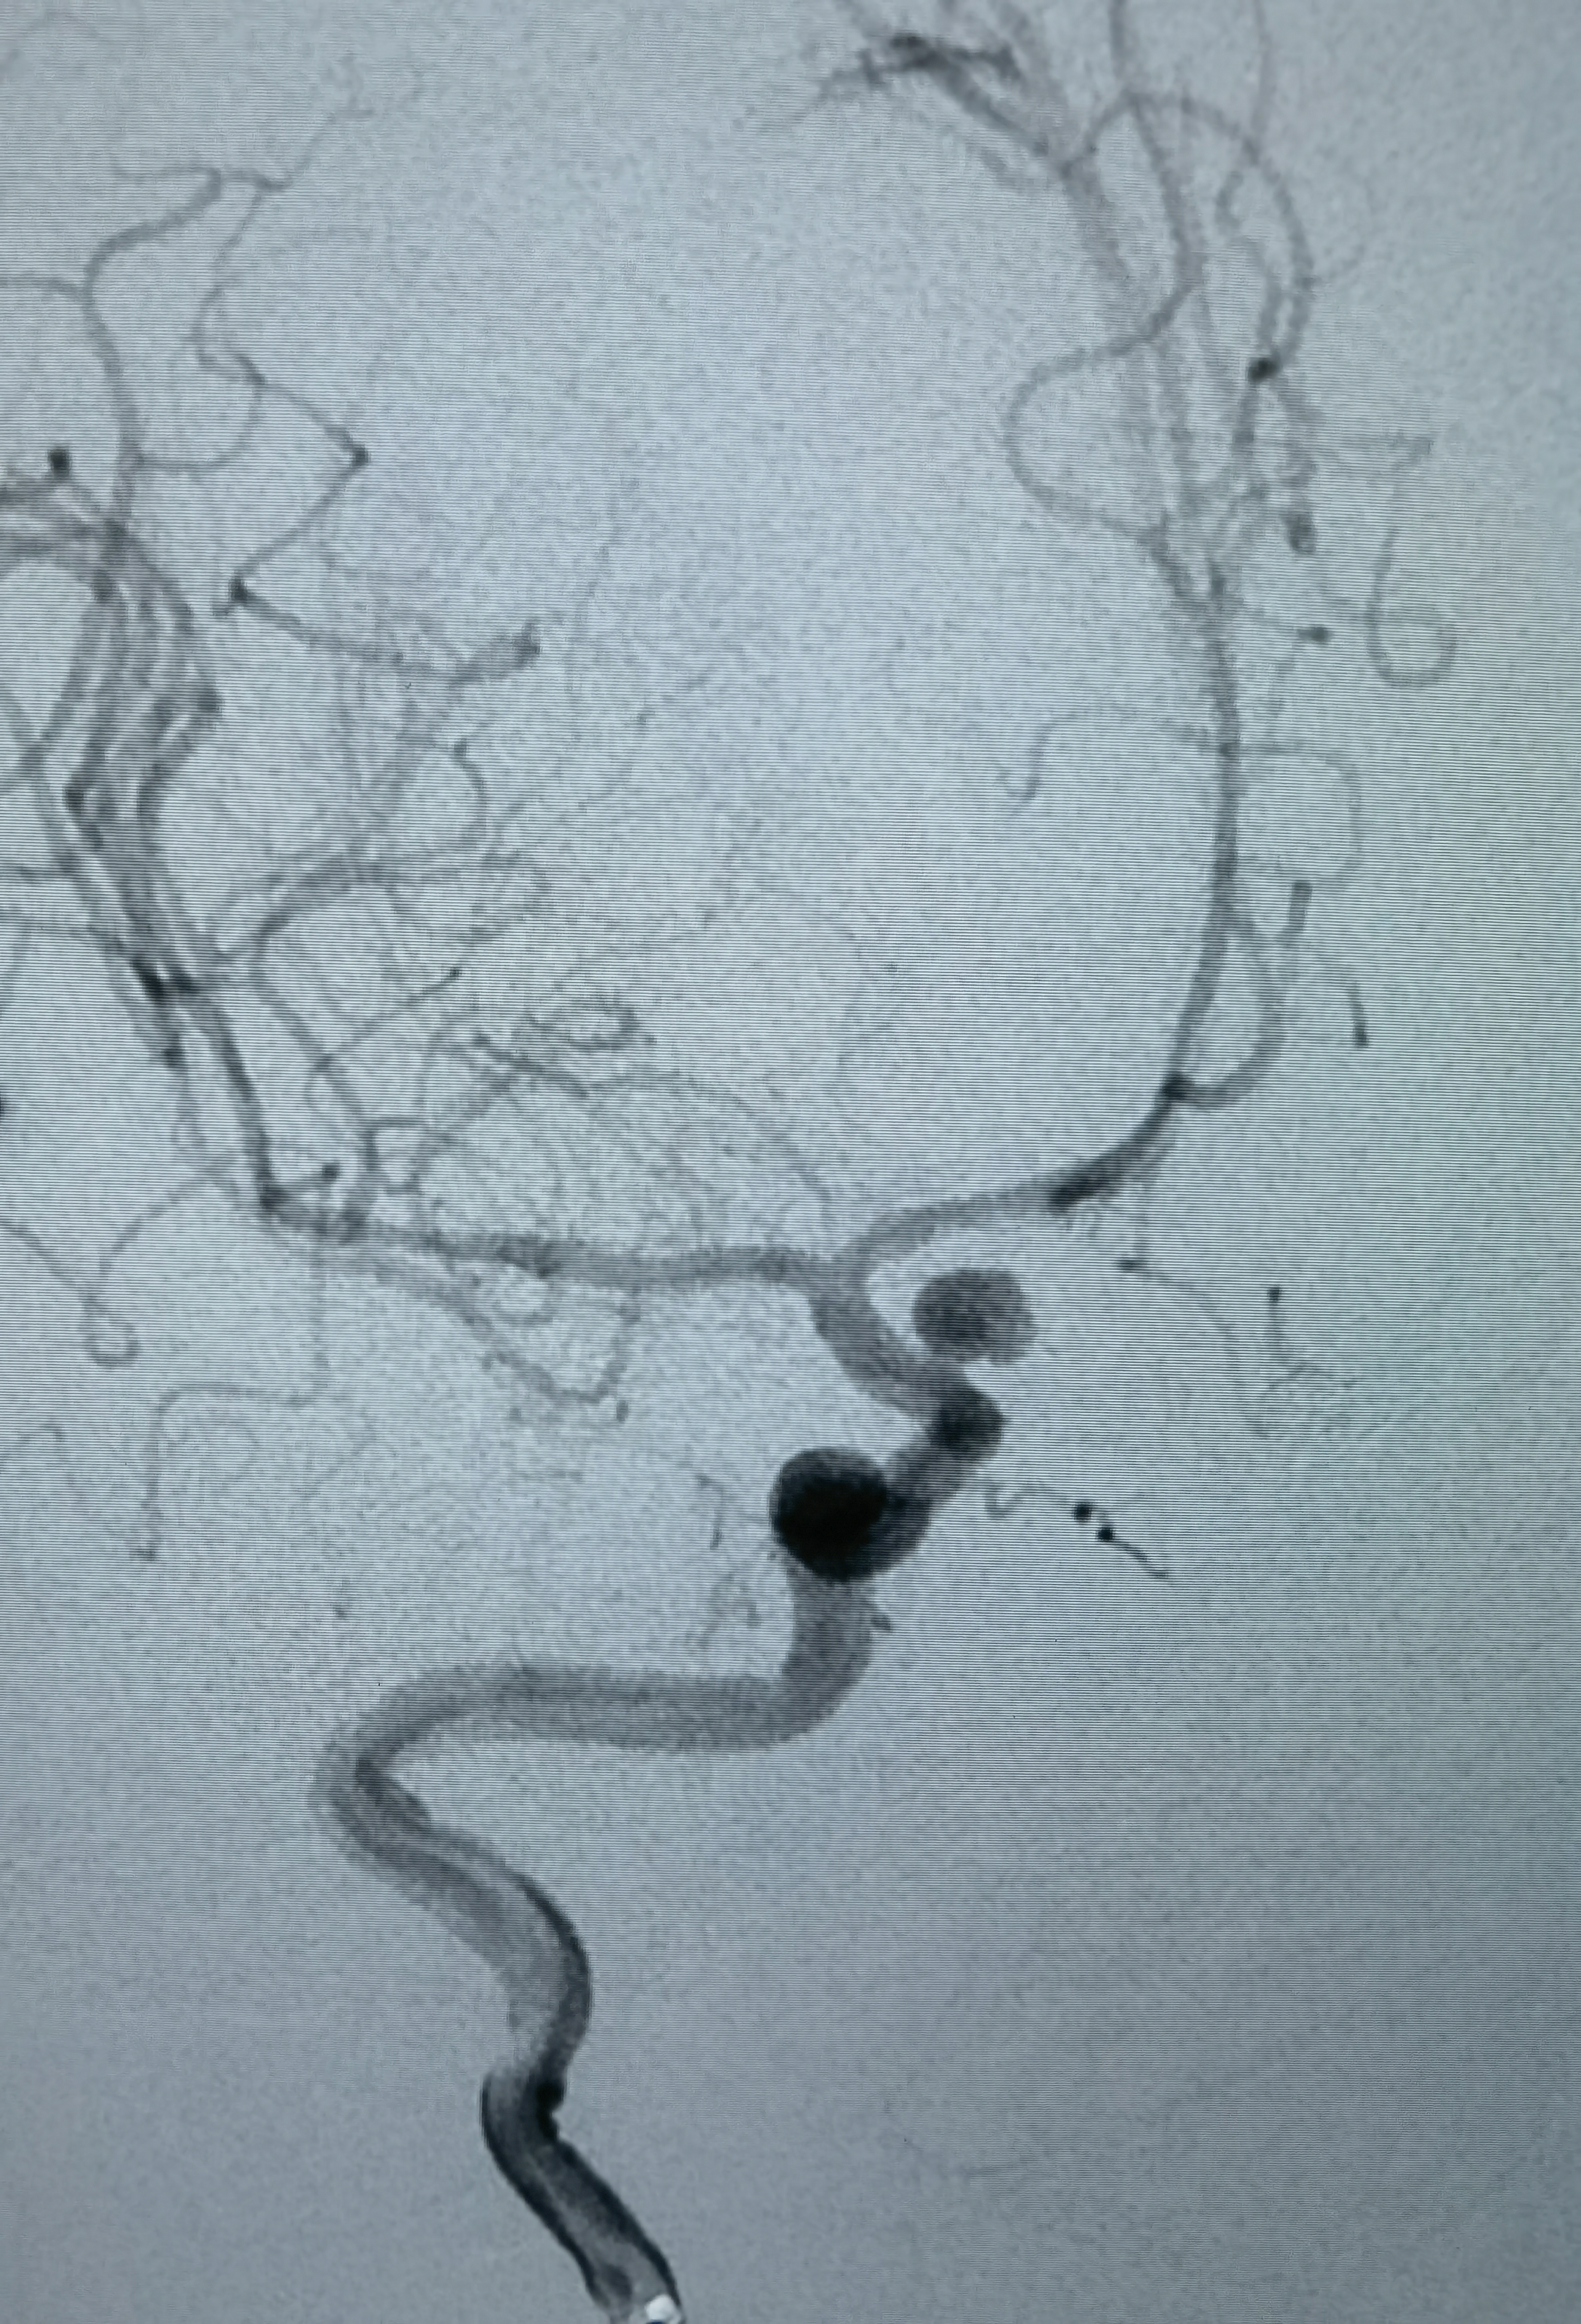

第三次出血后急诊上台,造影显示动脉瘤增大

工作位造影,瘤体约6.1*5.5mm,更加确认是血泡样动脉瘤!

3D成像!